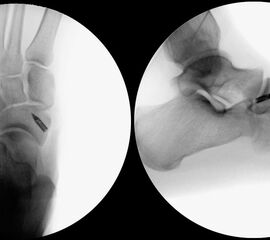

- Röntgenaufnahme des Fußes in 2 Ebenen unter Belastung und die unbelastete Schrägaufnahme (Supinationsaufnahme).

Radiologische Einteilung (Abb. 2)2:

Typ I: Ovalär bis rundliches, glatt begrenzter akzessorischer Knochen im Sehnenansatz des musculus tibialis posterior liegt.

Typ II: Trianguläres Ossikel, welches eine knorpelige Verbendung (Synchondrose) zum Os navicularis pedis hat. Typ II ist die häufigste Variante 2.

Typ III: Nach medial erweitertes Os naviculare im Sinne eines Os naviculare cornutum (entspricht einem fusioniertem Typ II).